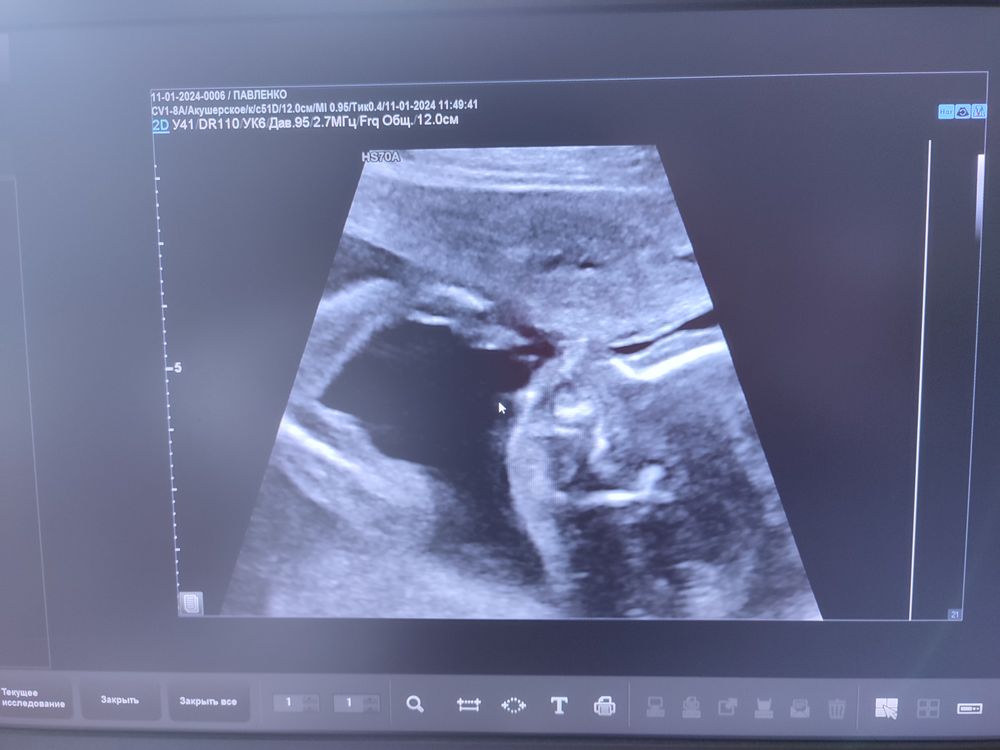

19н 3д: прошли второй скрининг... 💙😍

Милый такой)) на фото как будто мускулистый такой парень)) у нас вот только со срока 5,6,9 и 12 недель фото, больше нет. Всегда умиляет, когда разворачивают экран на узи и доктор рассказывает: вот на вас смотрит, вот щёчки,вот глазки. На предпоследнем узи так насасывал пуповинку 🥰 меня доктор в шутку спросила, кормила ли я ребёнка сегодня 😄 хорошо,что придумали узи когда-то. )) хоть маленько подсмотреть можно чем малыши занимаются)) Пусть и дальше всё идёт хорошо 🙏

Боже, как это мило, и улыбка до ушей и глазки влажные 🥰🤗🥹 А какое фото, снимки УЗИ малышей - это отдельный вид прекрасного 😍 Пусть и дальше мальчишка радует своих родителей 🙏